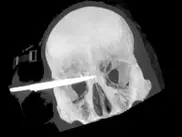

Новозеландец выжил после ранения в голову 9-сантиметровым ножом Новозеландец выжил после ранения в голову 9-сантиметровым ножом Лезвие ножа прошло в двух миллиметрах от глазного яблока и в двух сантиметрах от головного мозга.